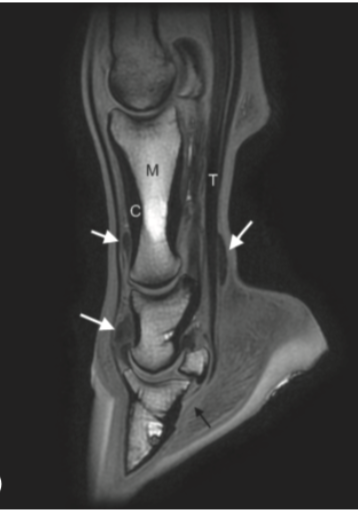

(Note hypointense fluid in DIP and NB - red arrows)

Appearance of fat and fluid on T2-weighted images

On T2 - 2 things are white; fat and water

Trabecular bone and synovial fluid are both hyperintense. The easiest way to distinguish T1 and T2 images is to observe the signal intensity of fluid.